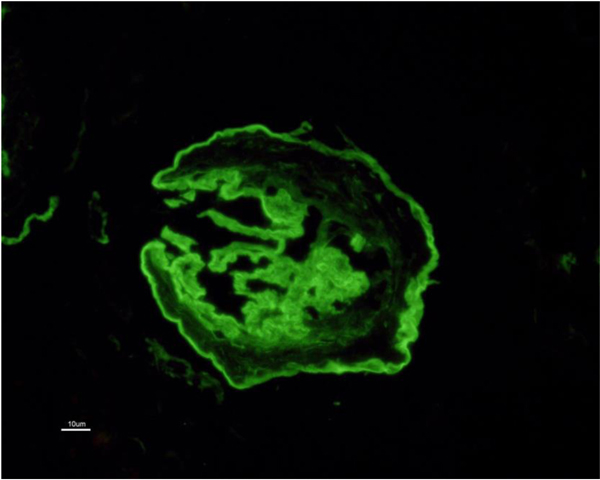

Allograft biopsy showed 7 viable glomeruli with active circumferential crescents in 5 (Fig. 1). There was a mild degree of tubulointerstitial chronicity. Immunofluorescence staining showed strong linear IgG along the glomerular capillary base ment membranes and occasionally along distal tubular basement membranes (Fig. 2). A diagnosis of Anti-glomerular basement membrane nephritis with crescentic transformation was made.

In view of the positive anti-GBM antibody, plasmapheresis was continued. In all, 23 sessions were given. However, the graft function did not improve and deteriorated relentlessly over the next six months. A repeat graft biopsy was performed 6 months later to the first biopsy and revealed fibrous crescents in all 8 glomeruli (Fig. 3) with moderate tubule-interstitial chronicity. Immunofluorescence continued to reveal similar findings as first biopsy (Fig. (4). She is currently on continuous ambulatory peritoneal dialysis, waiting to receive a deceased donor kidney.